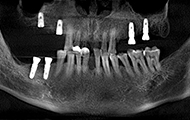

老爷子我做种植牙的费用明细想公开一下,我长期缺牙所以骨量都萎缩了,所以选了比较好的种植体,费用是六个种植体和基台,加上八颗全瓷牙冠,植骨手术和骨粉骨膜的费用另外算。所以呢,年轻人啊,缺牙了就赶紧去种牙吧,别选不合适的镶牙方法,年纪轻轻呢,后半辈子比我更精彩,何必搭上剩下健康牙齿的幸福?种植牙和镶牙之间,你们还是种牙吧。

过去十天了,今天去拆线,然后歇上一段时间,我的手术创口比较多,难免要缝合。种植体重新拍摄了CT,植入良好,医生今天给我检查,种植牙术后并没有肿胀,恢复的还算不错,看来我老骥伏枥,体质还不错,也感谢医生种牙技术的高超,种植体都是微创的手术,种植牙的创口减小了,种植牙术后就更容易恢复了。